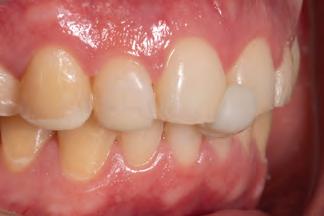

A 31-year-old woman presented with cosmetic concerns regarding her smile and requested a conservative enhancement. After clinical and radiographic analysis, digital 35mm photographs were taken and reviewed by the restorative clinician, technician, and surgeon (Fig 1). A digital impression was taken of the maxillary and mandibular arches using an intraoral scanner (Trios 3, 3Shape; Fig 2), and a smile design was developed with NemoSmile Design 3D software (Nemotec; Fig 3a). This allows for a facially driven smile frame to be created using reference lines of facial and smile proportions and natural teeth shapes and textures from the digital library (Fig 3b).

After developing the simulated mock-up, a 3D-printed resin model was created using CAD software (Fig 4a), and a clear PVS matrix (Exaclear, GC America) was fabricated to replicate the printed diagnostic wax-up using a nonperforated tray (Fig

Fig 1 Preoperative clinical views of a 31-year-old woman presenting with diastemas and limited tooth visibility. (top) Portrait. (center row) Intraoral views. (bottom row) Smile.

4b). This matrix was used to create an intraoral motivational mock-up with bis-acryl composite (Luxatemp Ultra, DMG). This additive mock-up provides the interdisciplinary team with an intraoral translation for evaluation (Fig 5). Upon evaluation of the digital smile frame and the clinical translation, it was determined that multiple esthetic and restorative requirements were necessary for an optimal biologic framework, and the interdisciplinary team determined the best sequence for these procedures. The patient was presented with the interdisciplinary treatment possibilities that included restoring the maxillary anterior teeth and premolars with a minimally

invasive preparationless procedure or with less conservative veneer preparations. The restorative materials discussed included injectable resin composites and ceramic (ie, feldspathic, pressable, machinable). For an optimal biologic framework and health, it was determined that connective tissue grafting would be necessary for treatment of the recessiontype defects on the maxillary left central and lateral incisors, canine, and premolars. The patient opted for the conservative preparationless composite veneers using the injectable resin technique followed by a connective tissue surgical procedure using the tunneling technique.